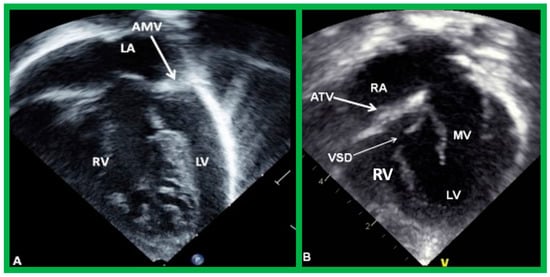

5.4. What Is the Status of Atrioventricular Connections?

After the visceroatrial situs and the ventricular locations are defined, the relationship between atria and ventricles should be assessed. These relationships are: concordant, with the RA emptying into the RV and the LA emptying into the LV (Figure 30A), and discordant, with the RA emptying into the morphologic LV and the LA emptying into the morphologic RV (Figure 39). Other AV connection abnormalities are: both the right and left atria emptying into a single ventricle (double-inlet left ventricle (Figure 30B)), both atria emptying into both ventricles via one common AV valve in the form of AV septal defect (Figure 42), a common atrium emptying into a single ventricle via a single AV valve (the so-called cor biloculare) (Figure 43), a common atrium emptying into inverted ventricles via a single AV valve (Figure 44) and atresia of either tricuspid or mitral valve (Figure 45). In addition, straddling or overriding of the AV valve over the ventricular septum may also occur. Such abnormalities may be defined by methodical echocardiographic imaging with the rare need for MRI, CT, and angiographic studies.

Figure 45. (A) Echo frames in apical four-chamber view of a patient with mitral atresia demonstrating atretic mitral valve (AMV), pointed out by an arrow in (A). A large right ventricle (RV), a small left atrium (LA), and a small left ventricle (LV) are also visualized. (B) Echo frames in apical four-chamber view of a patient with tricuspid atresia, demonstrating atretic tricuspid valve (ATV) shown by the thick arrow in (B). Dilated LV, a small RV, and moderate-sized ventricular septal defect (VSD; thin arrow in (B)) are also seen. Mitral valve (MV) and right atrium (RA) are labeled.